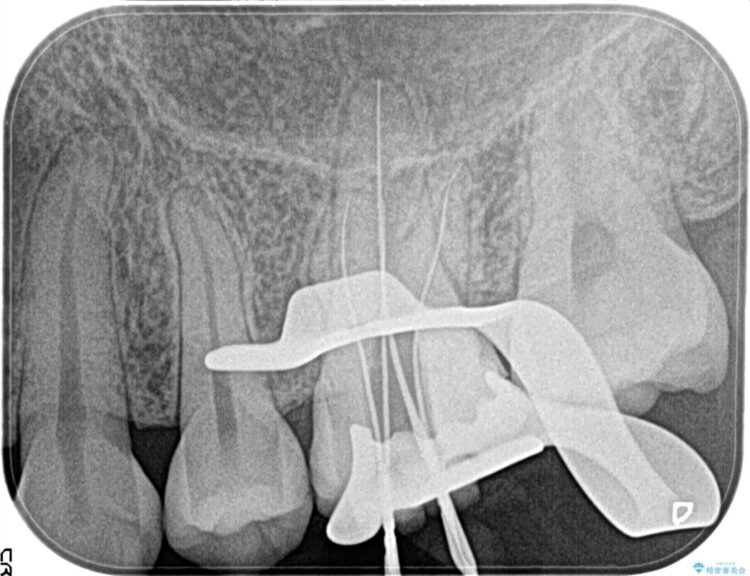

検査の結果、歯髄の炎症が進行し、痛みや歯の揺れなどの症状が出ている(症候性不可逆性歯髄炎)ことに加え、炎症が歯根の先端まで広がっている(症候性根尖性歯周炎)ことがわかりました。そのため、歯髄を除去する処置である抜髄を行いました。

今回の患者さんのケースでは、歯髄の炎症が歯根の先端まで広がっていたため抜髄を行いましたが、抜髄後は被せ物などの治療が必要になります。